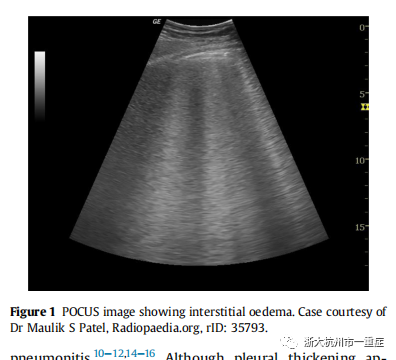

间质综合征是指肺间质发生水肿、感染、浸润。在COVID-19中,间质综合征很可能是由急性呼吸窘迫综合征(ARDS)或肺炎引起的。间质综合征的特点是B线(Figure 1),这是肋骨间的垂直高回声信号,与正常肺部看到的水平A线相反。此外,胸膜下实变表现为B线周围模糊不清的高回声区域。严重病变时,实变可能类似于肝脏,这被称为肺肝样变。尽管B线是非特异性的,但其在COVID-19中很常见。Peng等人首先报道了B线的外观,其他团队也证实了这一点。在具有明显水肿或实变的严重疾病中,可能会出现“白肺”。